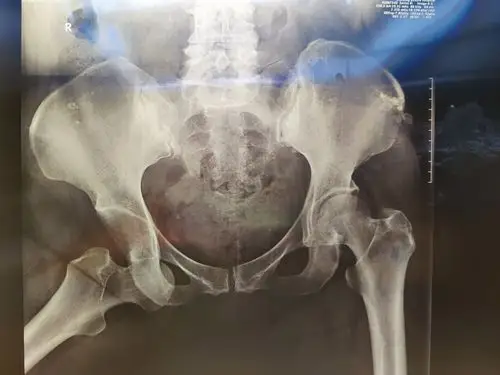

髋关节前脱位手法复位一例

典型的髋关节脱位

髋关节中心脱位伴髋臼骨折一例柏乡县中心医院骨科